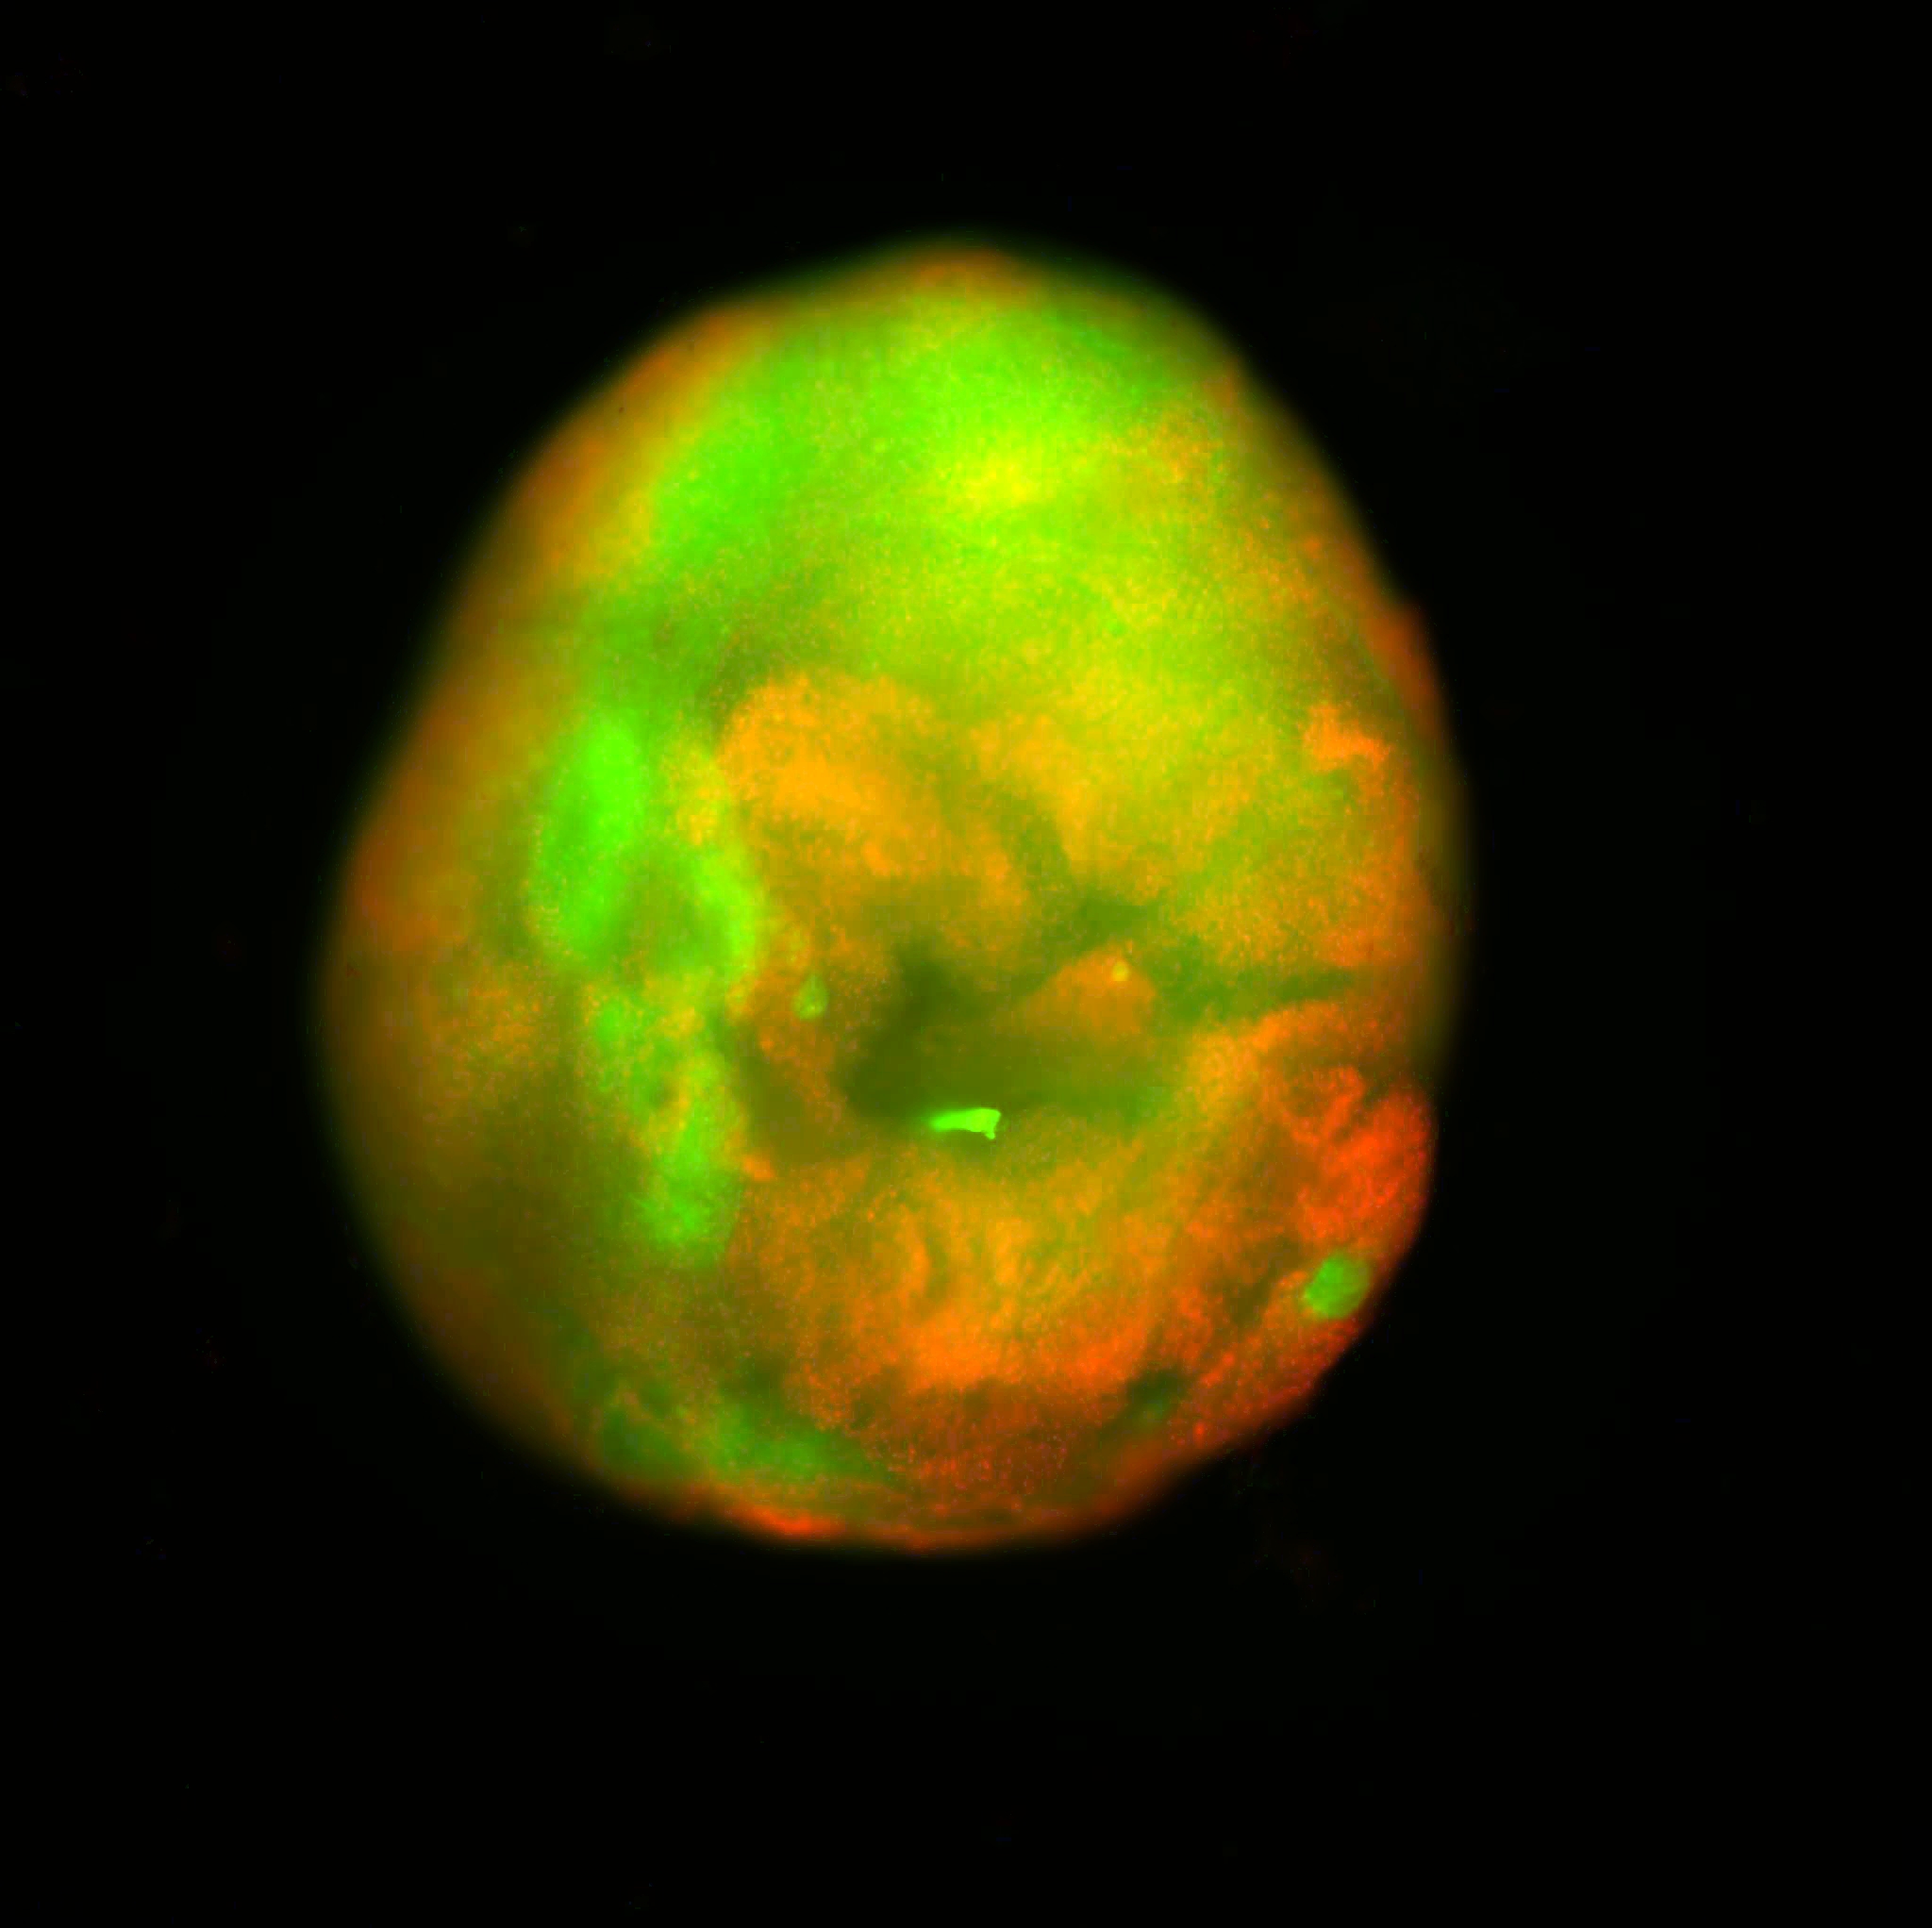

これは、脊髄オルガノイドのモデルの画像。赤い細胞は死んでて、緑の細胞は生きているよ!